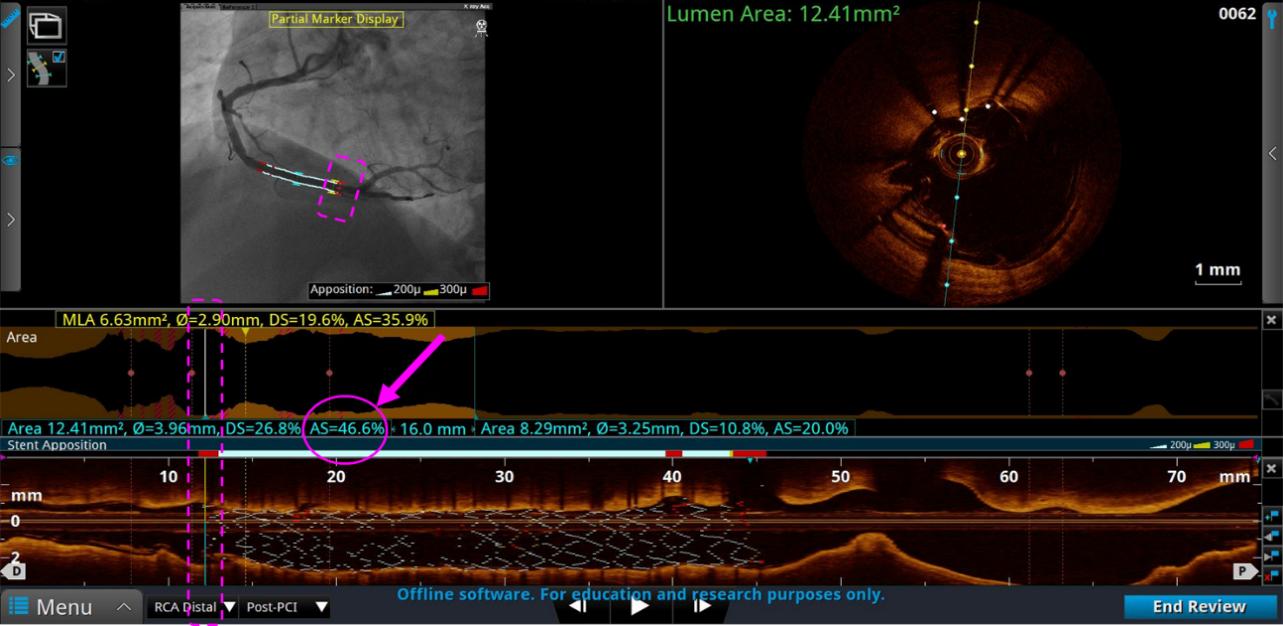

2、ACR造影融合——评估支架扩张情况

远端评估:支架远端边缘如果AS(面积狭窄率)≥20%,则需要进一步扩张处理。

近端评估:支架近端边缘如果AS(面积狭窄率)≥20%,则需要进一步扩张处理。